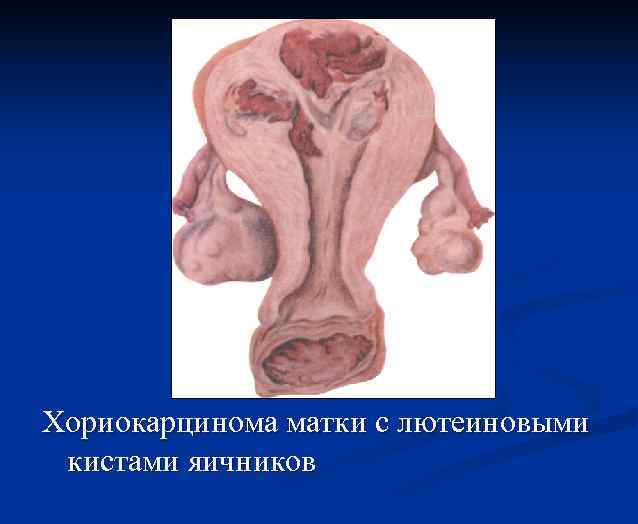

Клиника n n Нарушение менструальной функции(у 53, 7 % позднее менархе). Несоответствие размеров матки предполагаемому сроку беременности (у 50— 86 % больных). Образование лютеиновых кист яичников (в 50 % случаев). Появляются в течение первых 2 нед. Наличие их служит неблагоприятным прогностическим признаком. Обратное развитие лютеиновых кист отмечается в течение 3 мес. после удаления пузырного заноса. Малигнизации пузырного заноса. Злокачественное течение трофобластической болезни отмечено у 44, 2 % больных с размерами матки больше предполагаемого срока беременности.

Хориокарцинома матки с лютеиновыми кистами яичников